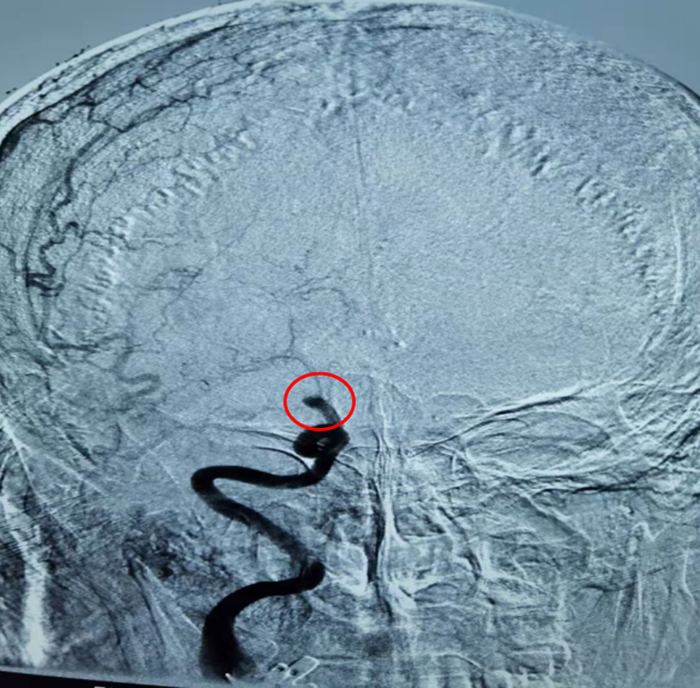

赵大爷第一时间被送入介入室。术中脑血管造影显示,赵大爷右侧颈内动脉闭塞,神经介入团队立即为他进行机械取栓,刘波通过快速抽吸,取出了大量暗红色血栓。仅35分钟,血栓全部取出,赵大爷大脑供血恢复正常。

造影显示:右侧颈内动脉末段闭塞